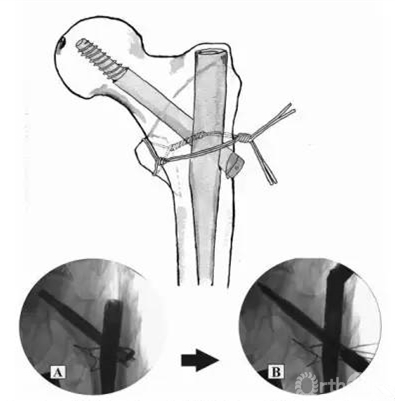

Fig.5.Make a anterior knot of candy-package ring.(A)Place two wires using a passer.(B)Twist two wires anteriorly.Then pull the wires inferioely.

Fig.6.Make a posterior knot of candy-package ring.Thereafter,reduction of lesser trochanter fragment using candy-package ring.(A)AP and(B)translateral image of C-arm intensifier.

Fig.7.Complete a candy-package wiring after IM nail fixation of fracture site.(A)IM nail fixaction and(B)fastening of candy-package ring under C-arm intensifier.